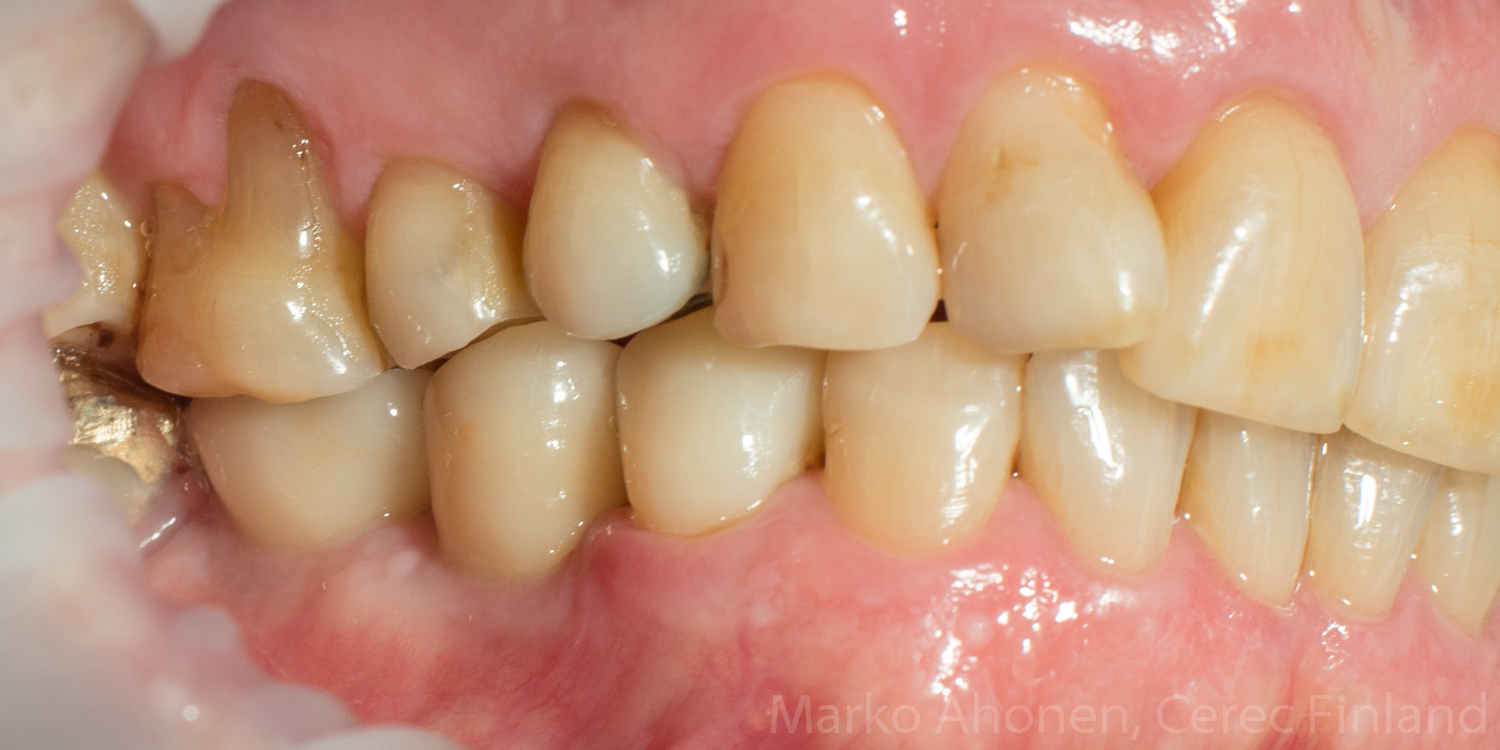

Potilaan vasemman alaleuan koko purenta oli ollut useita vuosikymmeniä sitten tehdyllä kultasillalla. Vanha silta oli hajonnut ja sivustan hampaat päädyttiin tekemään implanteilla ja keraamisella kruunulla. Kultasilta oli alunperin tehty huonoon purentaan tai silta oli taipunut ajan saatossa (yläleuan hampaat olivat voimakkaasti ylipuhjenneet). Potilas oli käyttänyt useita vuosia purentakiskoa, mutta hartioiden ja pään alueen kivut vaivasivat ajoittain.

Purentatasoa hiottiin huomattavasti ylöspäin, mutta ihan normaaliin speen-kaareen ei päästy (elossa olevaa vastahammasta ei voi loputtomasti hioa).

Valmiit implantit ja kruunu suussa (kontrolli 1kk hoidosta):

IMG_6352 IMG_6343 IMG_6349 IMG_6358

Varsinaisesti hartioiden ja pään alueen kipuja ei tässä hoidettu mutta potilas kertoi että kaikki vaivat lähtivät kun purenta laitettiin kuntoon. Purentakisko jätettiin pois koska potilaasta purenta tuntui niin hyvältä ja hampaiden öiseen aikaan tapahtuva narskuttelu jäi pois kokonaan.